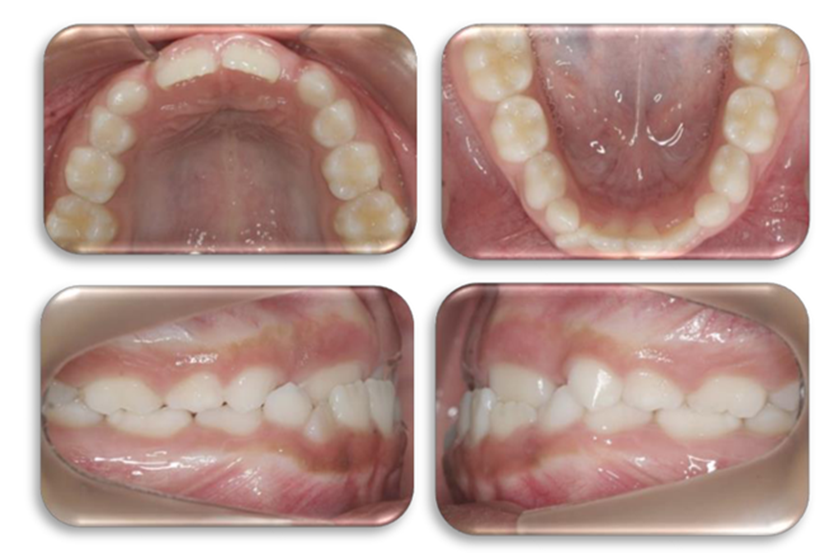

Autor: María Gabriela Flores Bracho. Fuente: Historia Clínica de J.I.F.A 7 años. 2012. Paciente con overjet de 4 mm, overbite de -1 mm, clase 1 Molares y caninos.

Autor: María Gabriela Flores Bracho. Fuente: Historia Clínica de J.I.F.A 7 años. 2014.

Paciente con overjet de 2,5 mm, overbite de 3 mm. Control post 16 meses.

Figura 19. Fotos intrabucales post tratamiento.